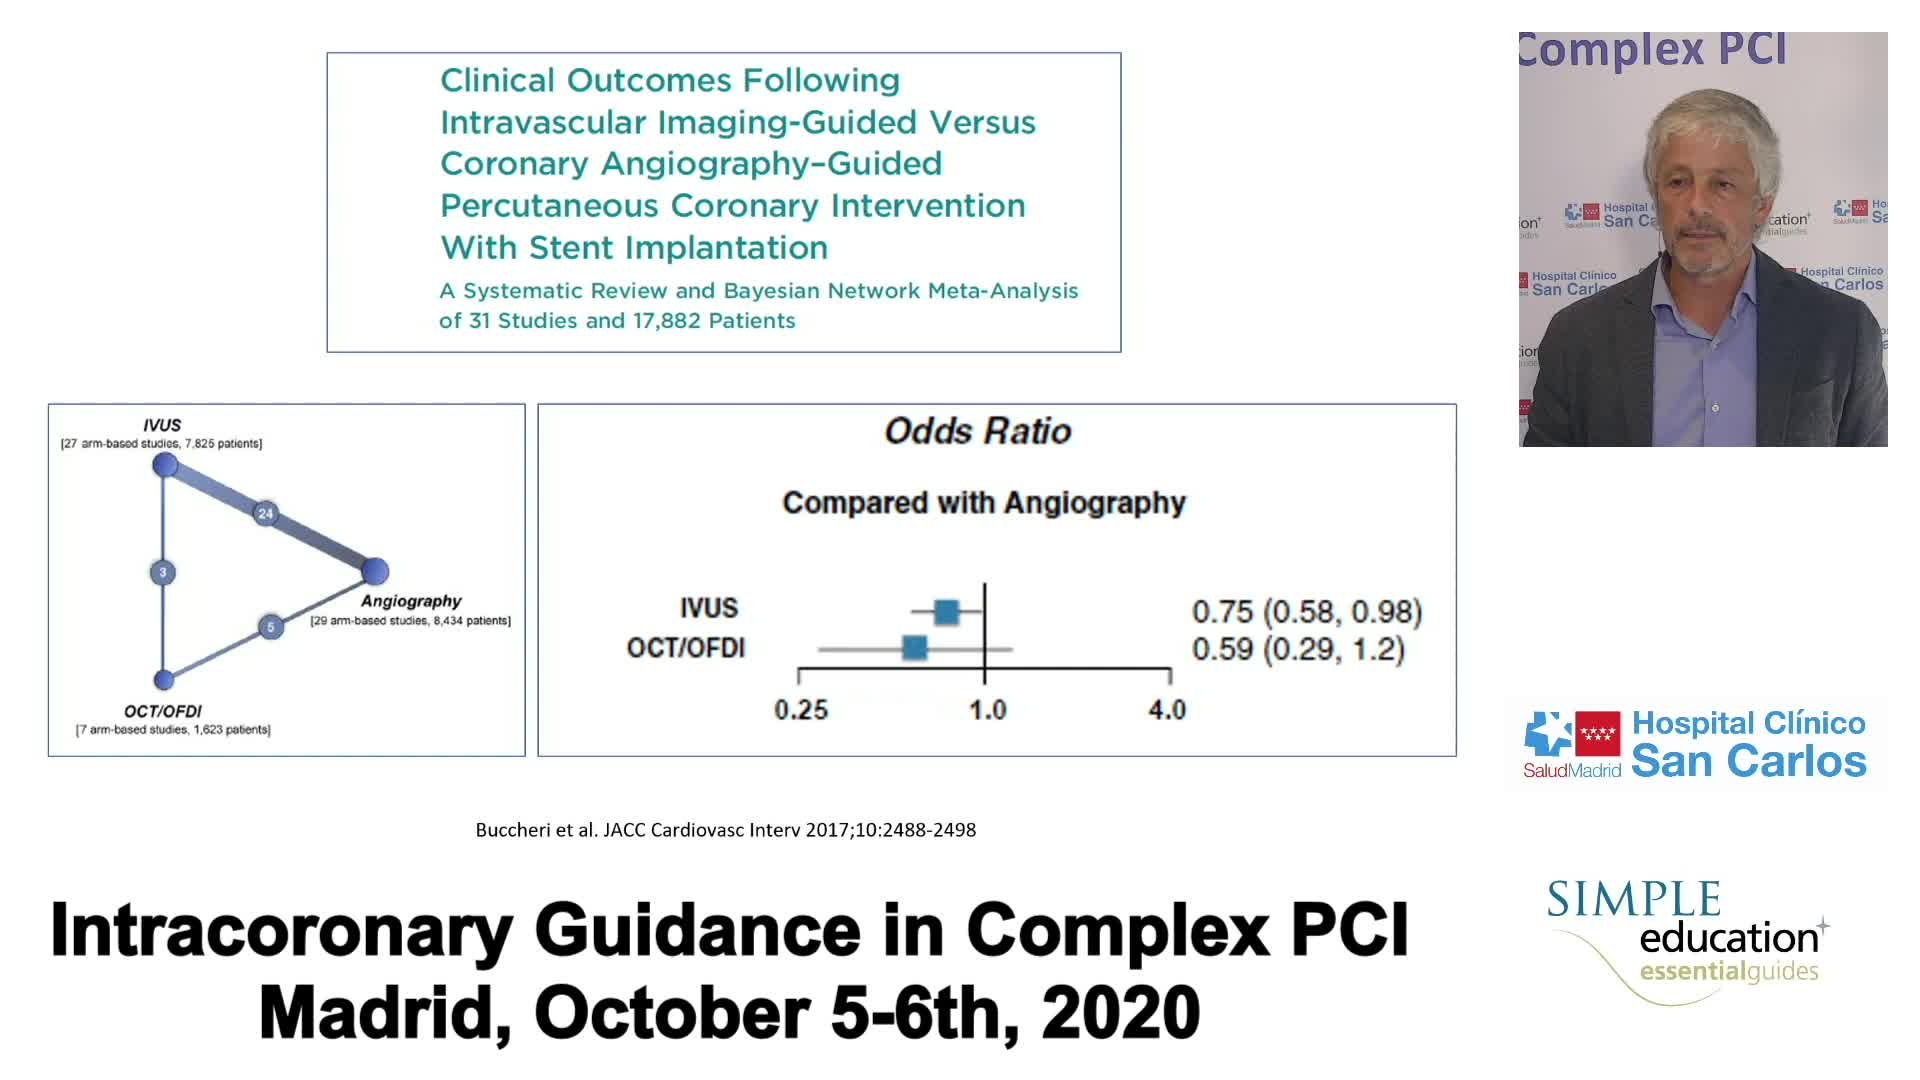

Evidence base for IVUS: to support use in routine practice - Prof Erick Schampaert

Advanced PCI Course Content

Best practices and personalised medicine in complex PCI - Prof Javier Escaned